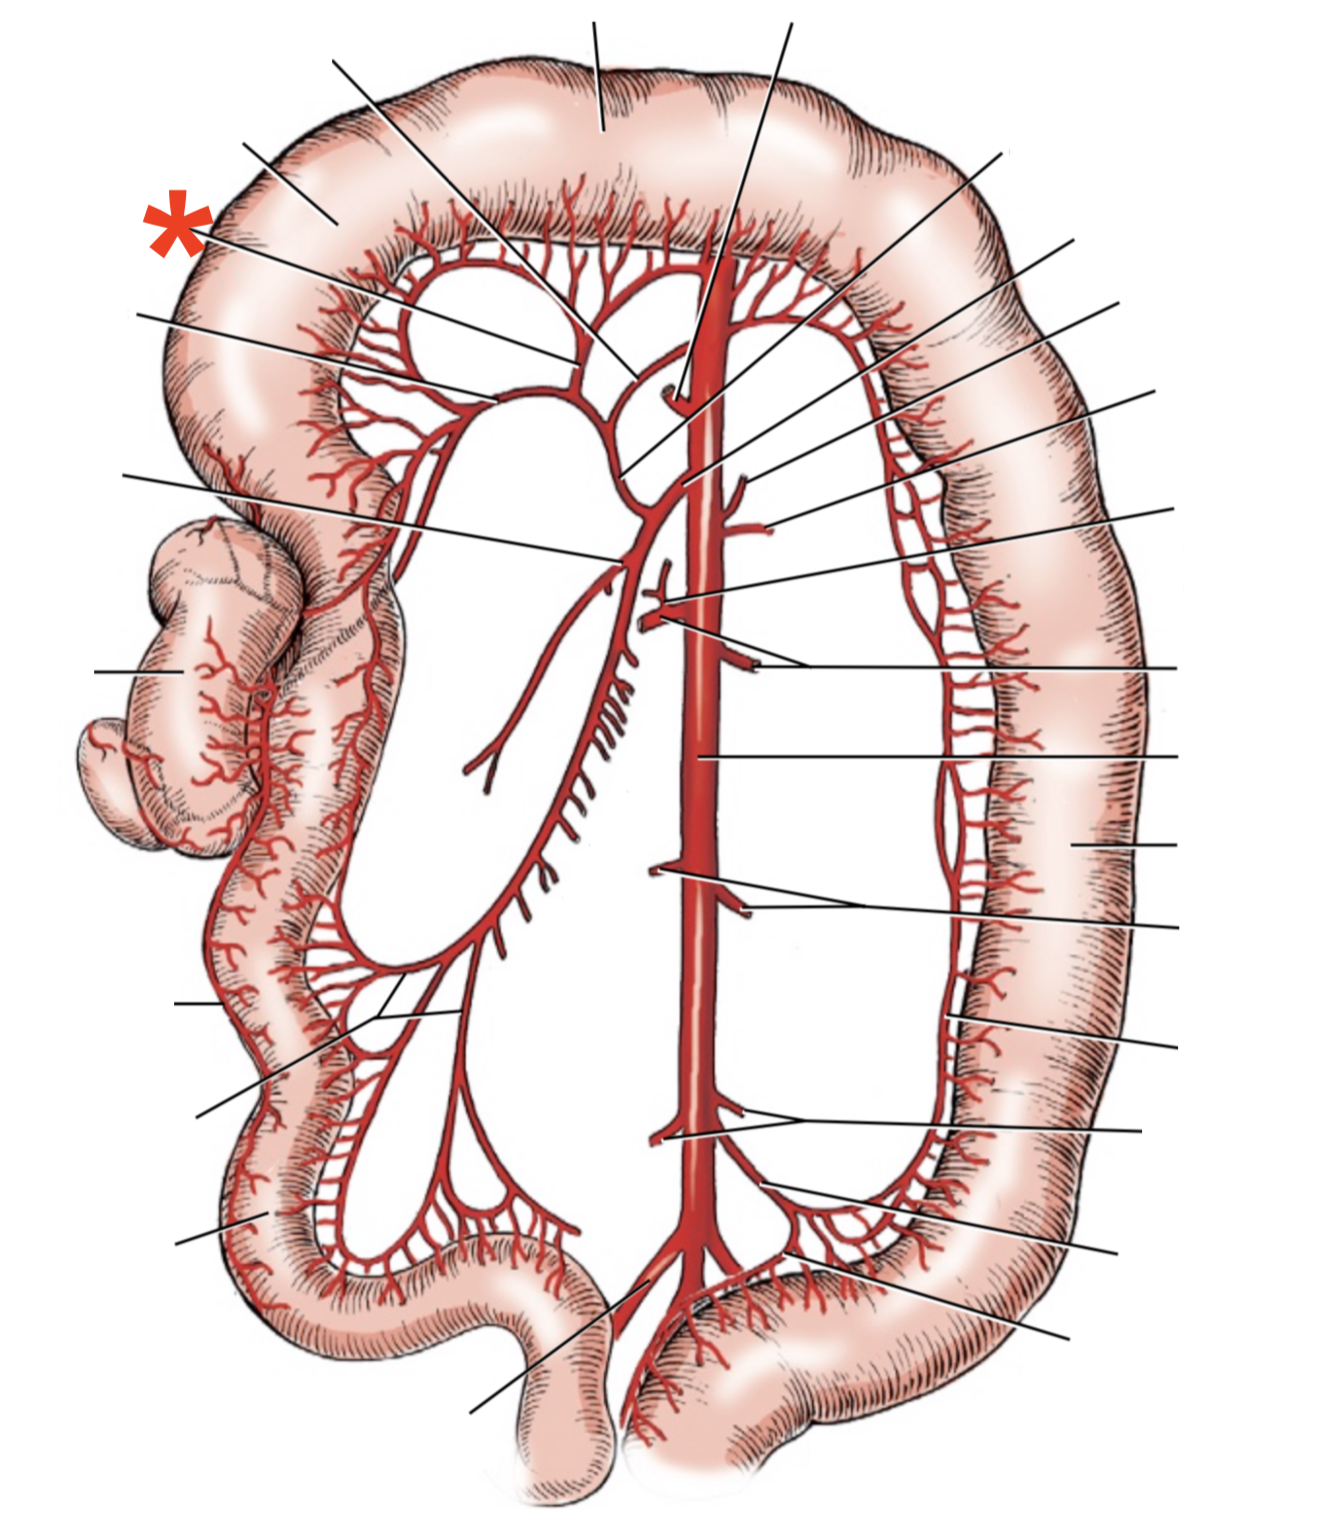

13

Q

A

A. mesenterica cranialis

15

Q

A

A. pancreaticoduodenalis caudalis

16

Q

A

Aa. jejunales

17

Q

A

A. ilei

- Anastomises with r. ileus mesenterialis a. iliocolica

18

Q

A

A. ileocolica

19

Q

A

A. colica dextra

20

Q

A

A. colica media

21

Q

A

A. mesenterica caudalis

22

Q

A

A. colica sinistra

23

Q

A

A. rectalis cranialis

List the branching of *a.* *mesenterica* *caudalis*

* *A. colica sinistra*

* *A. rectalis cranialis*

List the branches of *a.* *mesenterica* *cranialis*

* *A.* *pancreaticoduodenalis* *caudalis*

* *Aa. jejunalis*

* *A. ilei*

* Common trunk

* A. colica media

* A. colica dextra

* *A. ileocolica*

* *R. ilei mesenterialis*

* *A. cecalis*

* *R. colicus*